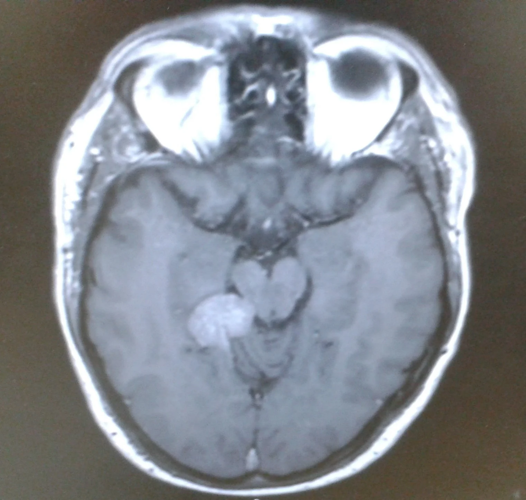

He was sent for further treatments and MRIs which revealed he had been living with an inoperable tentorial meningioma – a slow-growing, low-grade tumor at the base of his brain.

Darren Harris's brain scan. (Brain Tumor Research via SWNS)

Darren was diagnosed in March 2015 and his treatment – gamma knife radiosurgery – uses over 300 beams of radiation to destroy tumor cells.